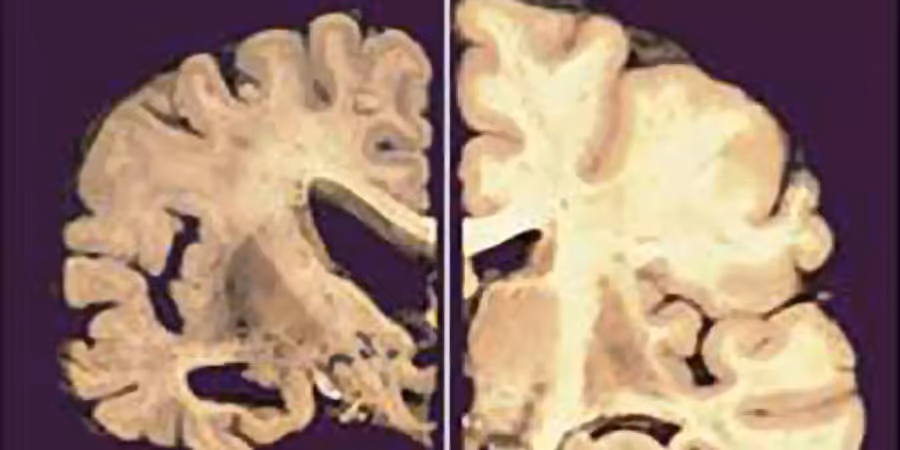

Aktuell sind schätzungsweise 131'300 Menschen in der Schweiz von Alzheimer oder einer anderen Demenzform betroffen. Im letzten Jahr kamen 31'200 Neuerkrankte hinzu.